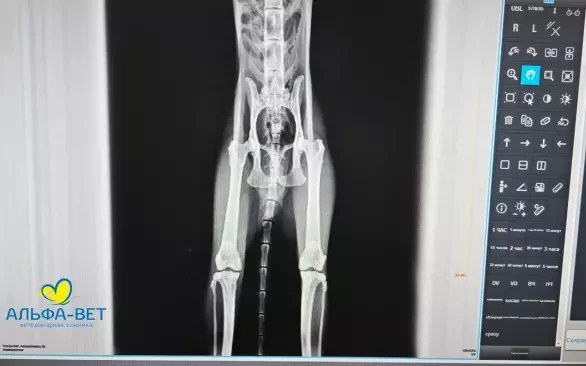

Участники получили возможность разобрать на практике алгоритм работы с рентгеновскими снимками и их описанием, рассмотрели типовые ошибки. Смогли закрепить на практике основные способы укладки питомцев, чтобы по возможности получать максимально информативные рентгеновские снимки.